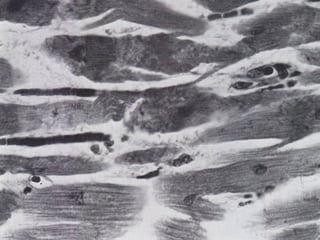

• #49 This is a microscopic section of the myocardium at magnification of 160 x showing wavy myocardial fibers in very early myocardial infarction.

• #50 This is a microscopic section of the myocardium at a magnification of 400 x showing pyknotic myocardial fiber nuclei. The wide spacing between adjacent myocardial fibers is indicative of myocardial oedema. These are both signs of very early myocardial infarction.

• #51 This is a microscopic section of the myocardium at a magnification of 1000 x showing contraction bands and granularity of cytoplasm in very early myocardial infarction.

• #52 This is a cut section of the myocardium at magnification of 160 x showing spotty scarring with isolated clusters of myocardial fibers . These are findings present in late myocardial infarction and could be the source of dysrhythmias and sudden unexpected death.

• #53 This is a microscopic section of the myocardium at magnification of 160 X showing radial zone of preserved myocardial fibers surrounding an obviously diseased small artery near a point of branching. The degree of myocardial ischaemia is less near the artery as compared to the area further away that shows only scar tissue. This can be seen in late myocardial infarction.